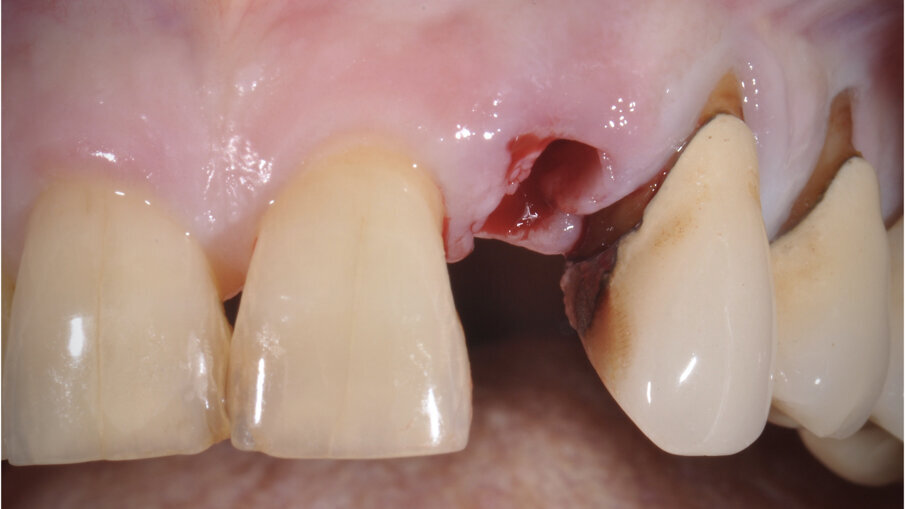

Il poter disporre di una tipologia di fixture estremamente orientata al conseguimento di elevati valori di stabilità primaria ha costituito un ulteriore elemento a favore di questa scelta. La paziente è stata sottoposta ad un trattamento preliminare a cielo coperto mediante levigatura radicolare. Il giorno dell’intervento, sotto profilassi antibiotica, è stata eseguita l’estrazione in maniera micro-traumatica e la rimozione mediante curettage dei tessuti infiammatori presenti. Non è stato eseguito un lembo di accesso, ma è stata verificata la presenza di tessuto osseo in sede vestibolare (Fig. 3).

Fig. 3_Alveolo post-estrattivo.